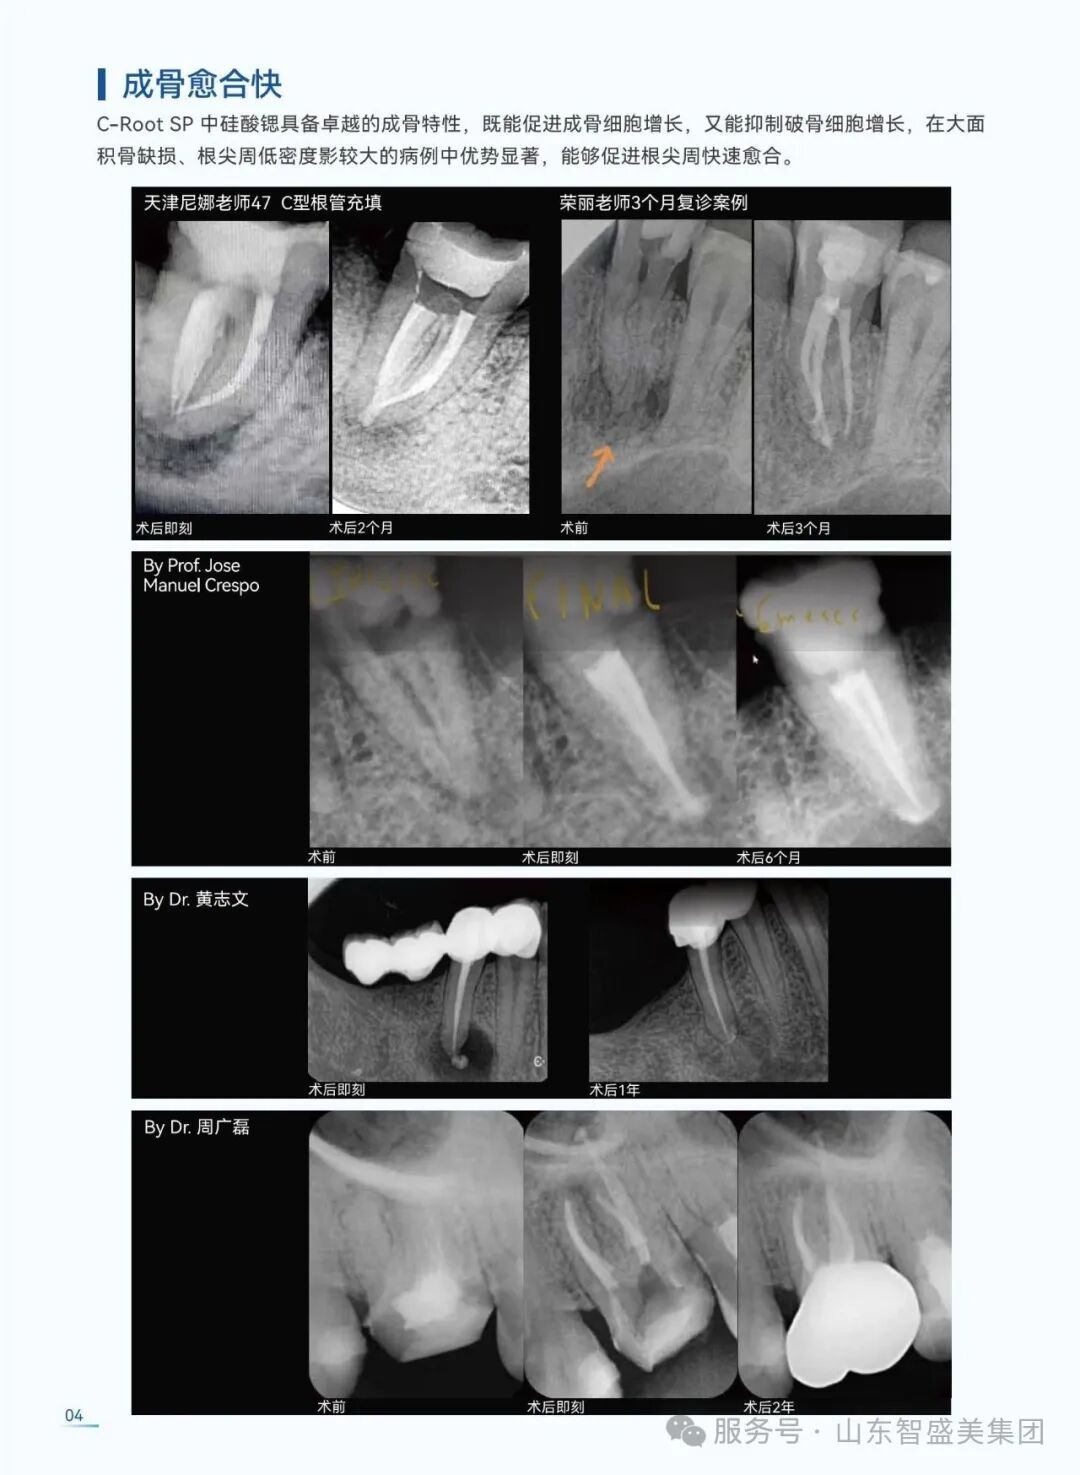

根管填充/修复